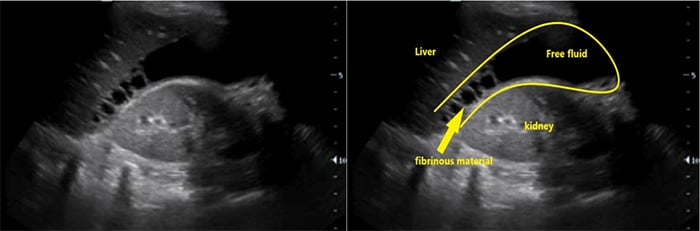

- Ascites (Fig. 6)

- Ascites is a common finding in many disease entities however in the patient with HIV from a TB endemic area, it is highly suggestive of TB.

- With or without fibrinous debris: OR 2.221

- Without fibrinous stranding: PPV= 73% NPV = 33%18

- With fibrinous stranding: PPV = 86% NPV= 41%18

Figure 8. RUQ free fluid with fibrinous stranding and hyperechoic liver lesions

- Hepatomegaly and hypo- or hyper-echoic lesions in the liver are commonly seen in HIV patients with EPTB but these findings are non-specific.23,24